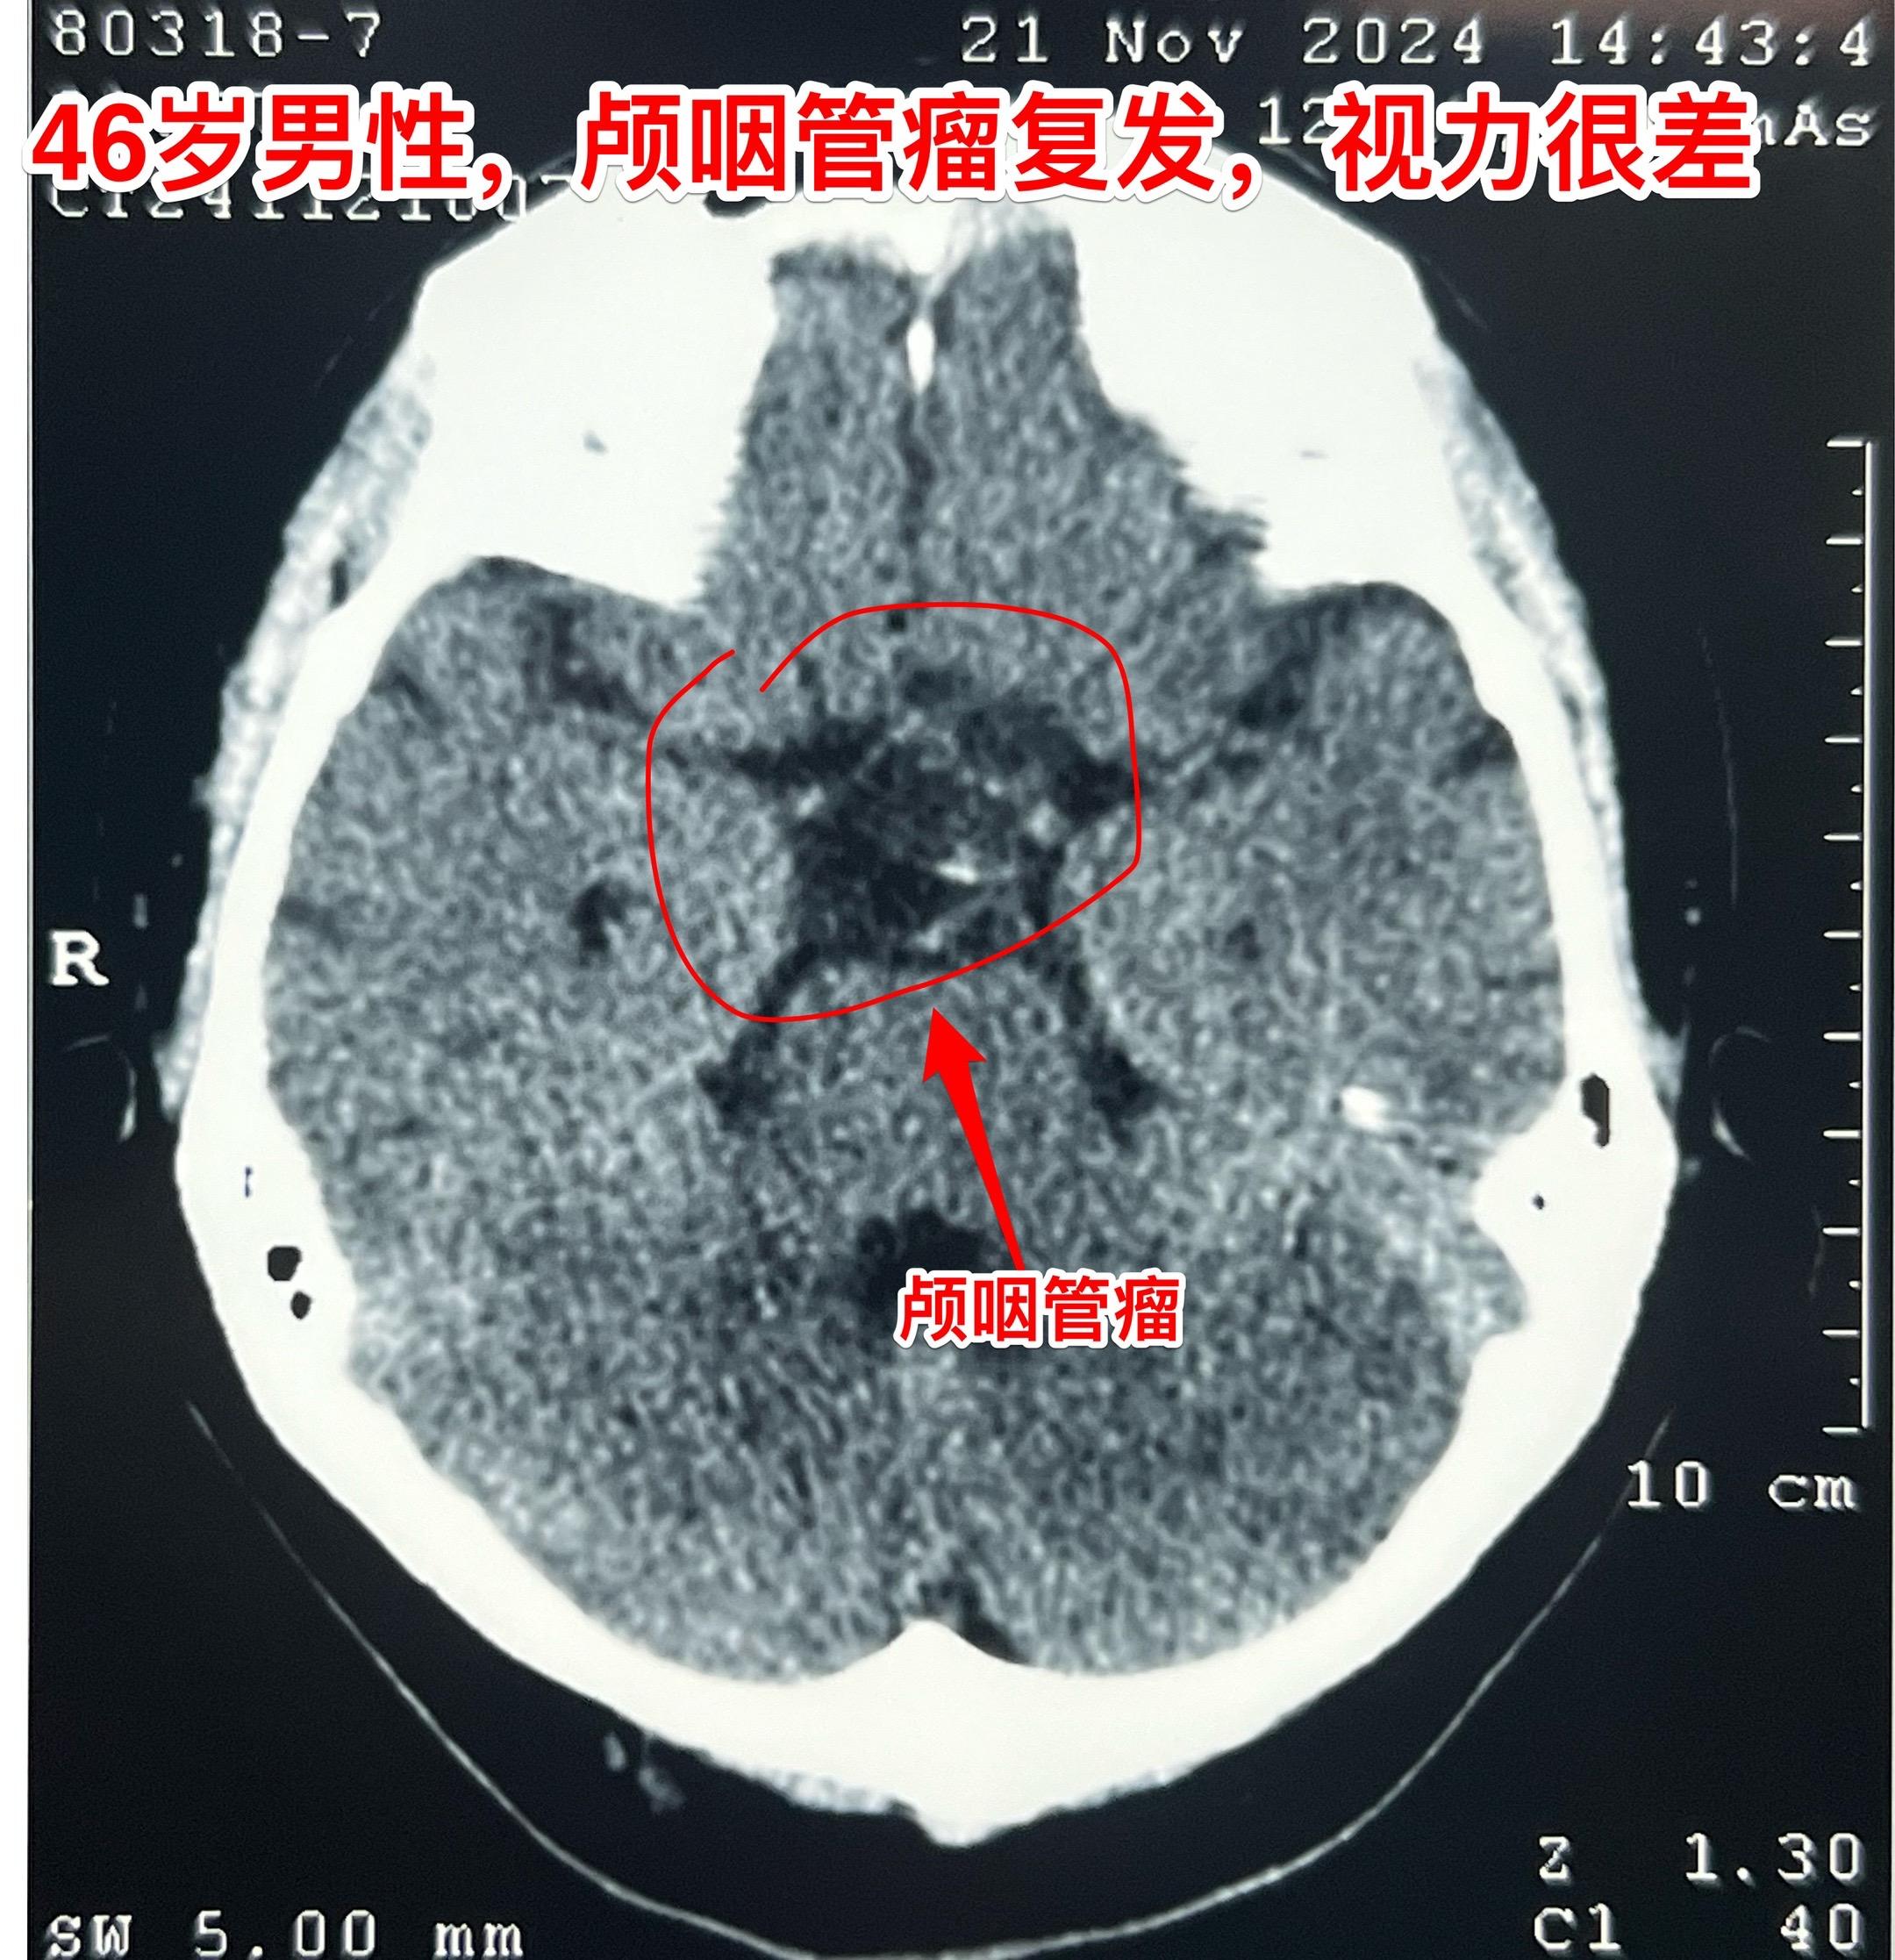

3月28日两个颅咽管瘤手术 两个都是经鼻手术手术后复发的颅咽管瘤手术。...

2025-03-30 12:09